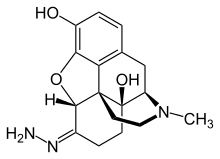

Several semi-synthetic opioids were developed in Germany in the 1910s. The first, oxymorphone, was synthesized from thebaine, an opioid alkaloid in opium poppies, in 1914.[228] Next, Martin Freund and Edmund Speyer developed oxycodone, also from thebaine, at the University of Frankfurt in 1916.[229] In 1920, hydrocodone was prepared by Carl Mannich and Helene Löwenheim, deriving it from codeine. In 1924, hydromorphone was synthesized by adding hydrogen to morphine. Etorphine was synthesized in 1960, from the oripavine in opium poppy straw. Buprenorphine was discovered in 1972.[228]